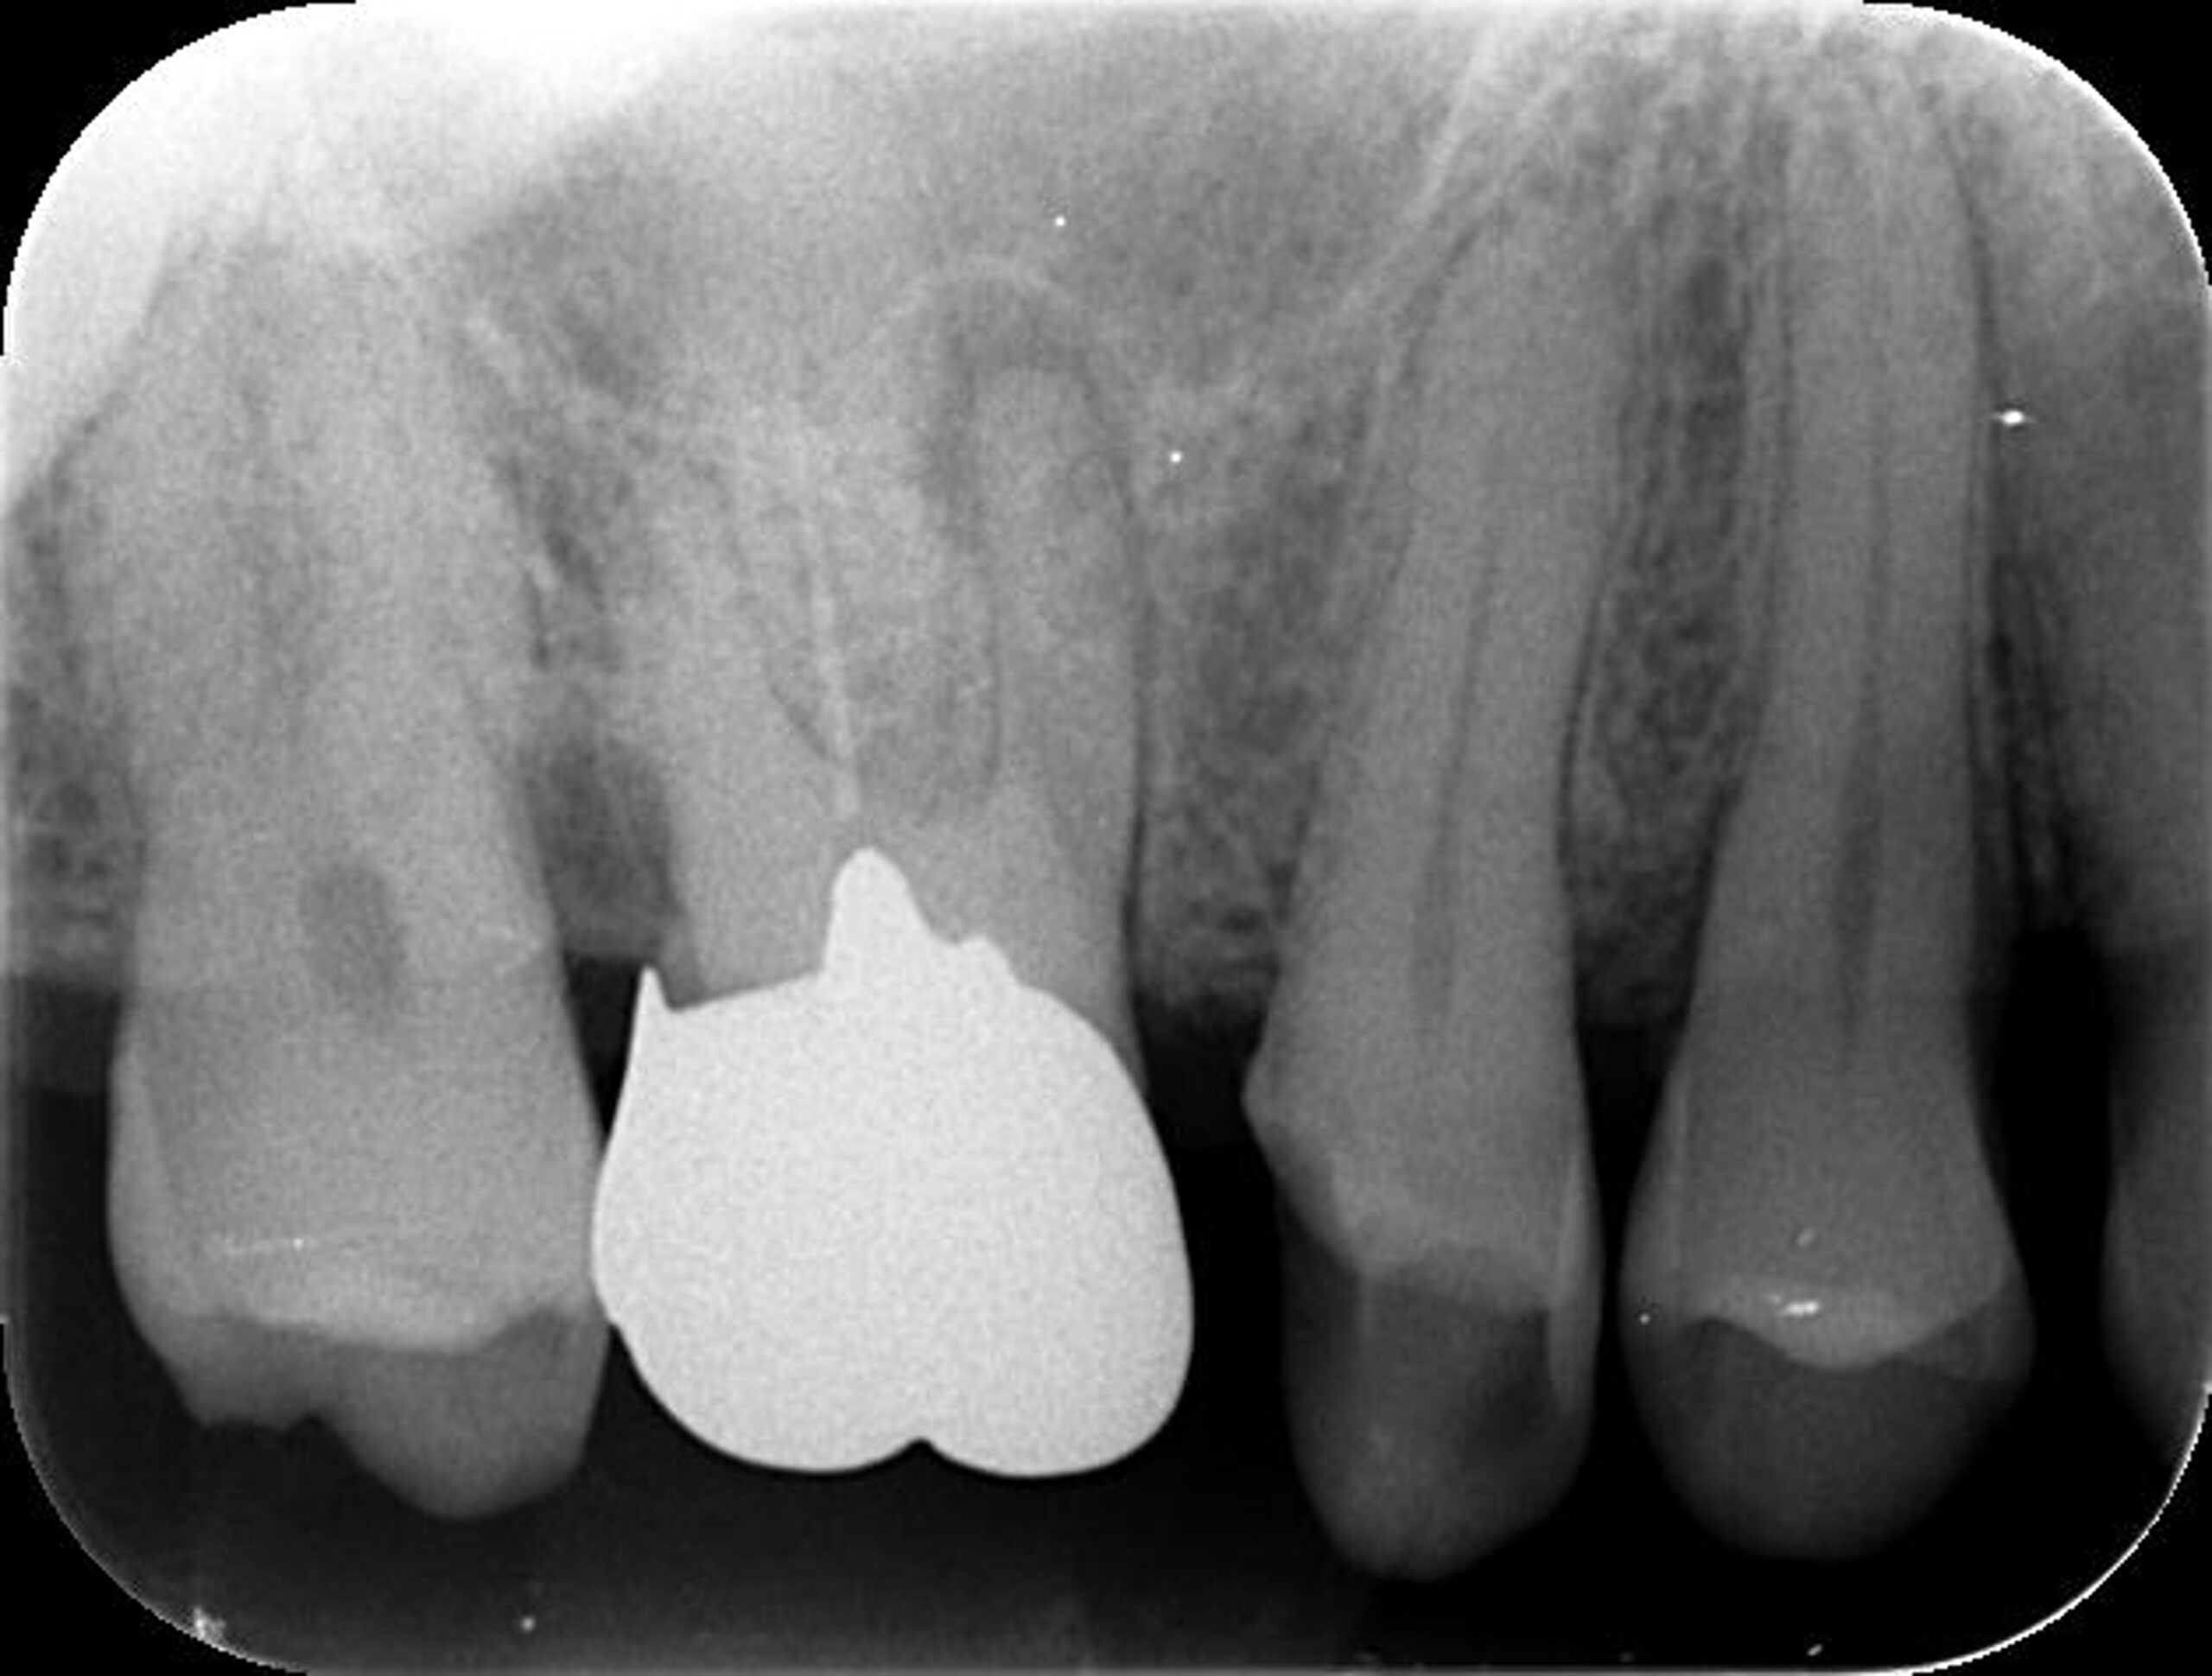

症例1:パーフォレーションリペア症例

(歯の中に大きな穴が空いてしまっているのを埋めて再生を促す治療)

歯に穴が空いていて骨に炎症がある状態 |

CTでも歯の周囲に骨がないのが分かる。 |

BEFORE |

AFTER |

| 医院の診断 | 虫歯の再発、慢性根尖性歯周炎、遠心根人為的穿孔 |

人為的根穿孔を起こした部分に感染を起こしており、歯周ポケットが9㎜ありました。 ラバーダム防湿とマイクロスコープを使用して丁寧に治療を行いました。 殺菌性があり歯を補強することのできるMTAという根管充填材料を使用して、歯周ポケットは2㎜に改善しました。 |